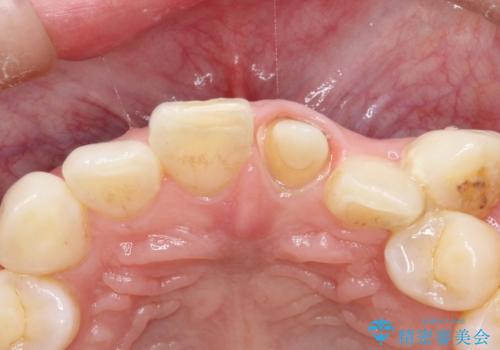

- 他院で前歯の変色をダイレクトボンディングにて修復治療しておりましたが、審美障害を主訴に来院されました。

根管治療後、オールセラミックにて治療を行っております。

ダイレクトボンディングはセラミックに比べ経年劣化しやすい材料です。

今回はオールセラミッククラウンによる治療を行いより審美的な修復ができました。